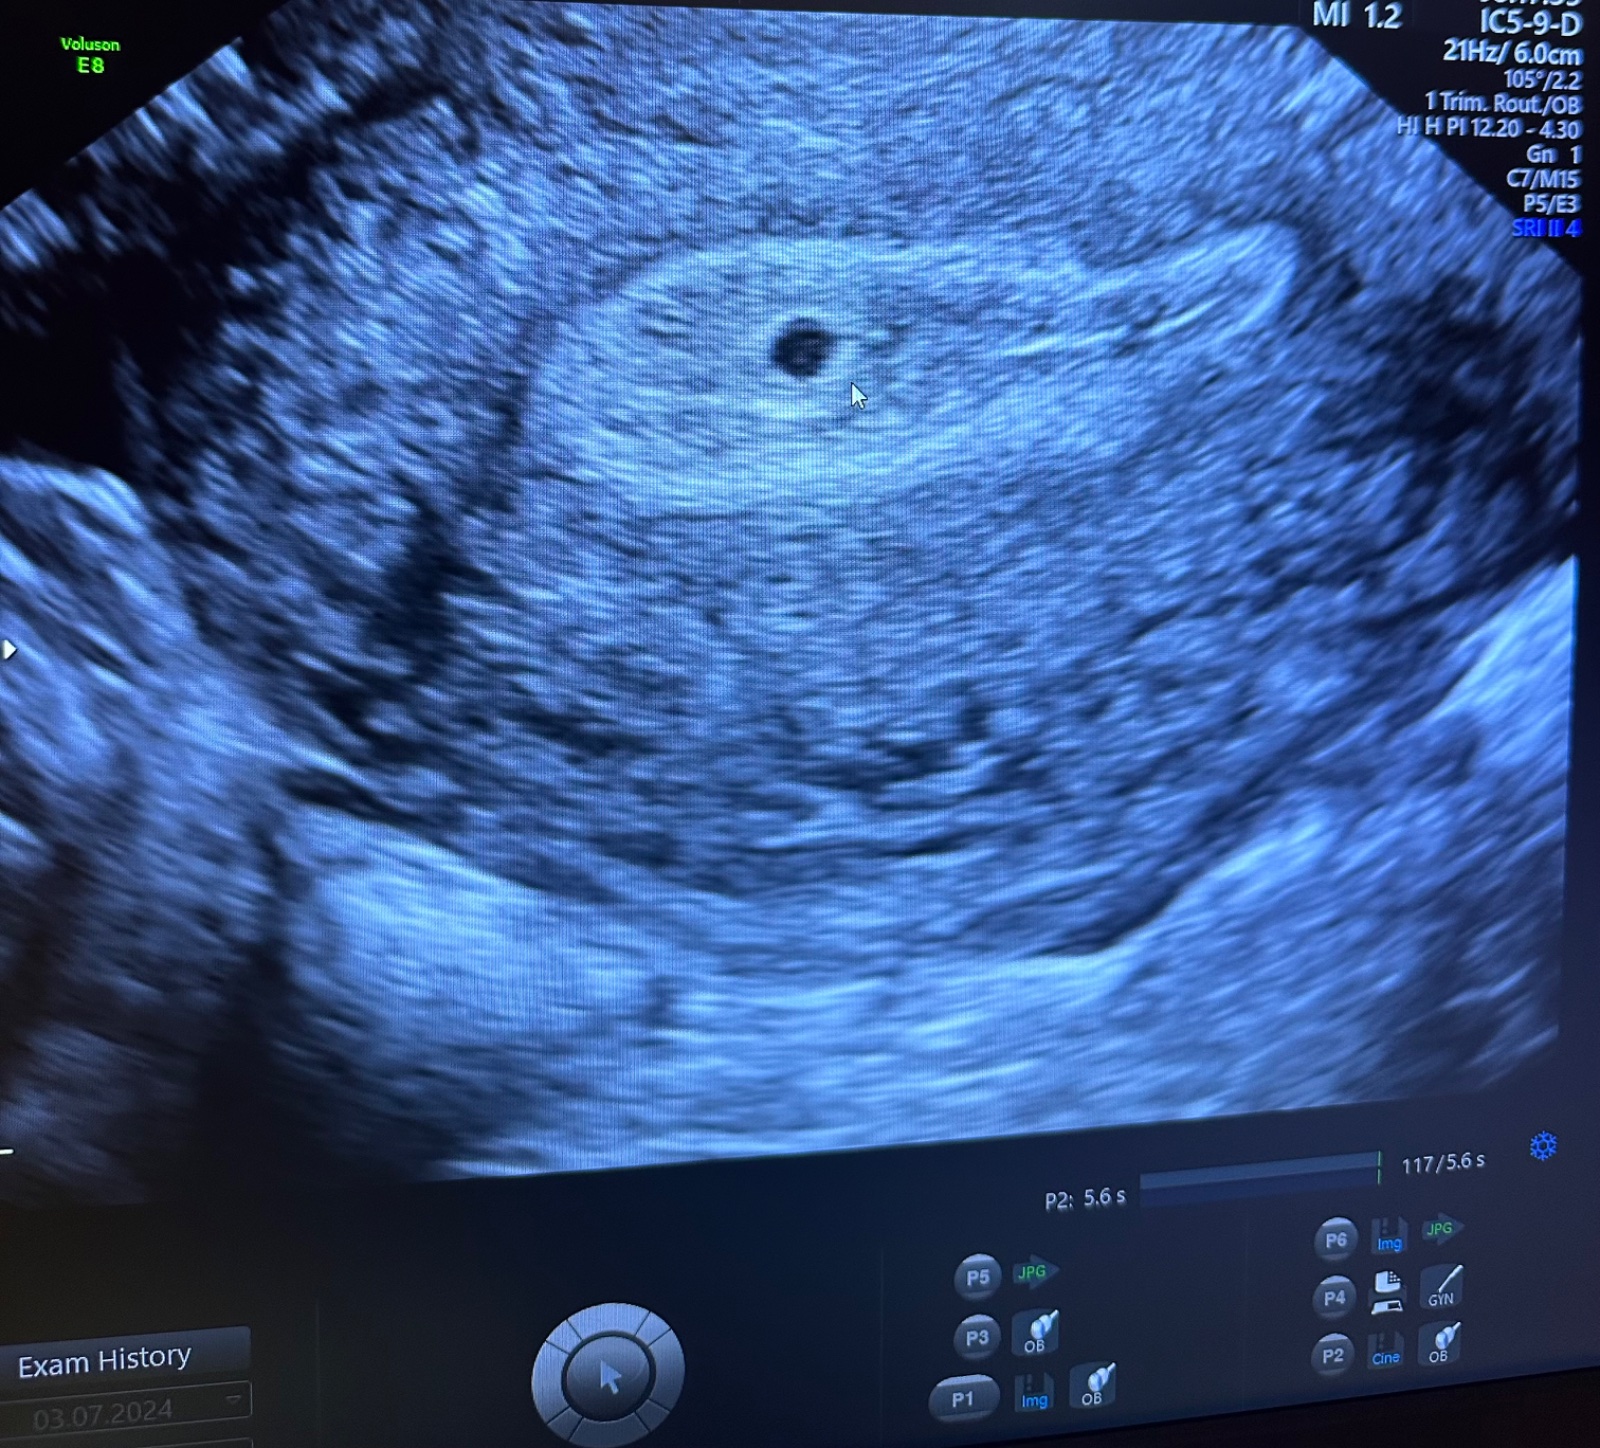

@nikadominikanika ahoj udes dnes k tomu dr? ja som tiez uz v cakarni, krv zobrata a vraj mi aj sono urobia som 16dpt tak som zvedava ci nieco bude vidiet🙄🙄

@jasmin_88 krásna foto ❤️❤️ nech malinké pekne rastie

@skrecok321 dakujem krassne 😍

aj hcg mi posielali pred chvilkou tak 16dpt - 1366